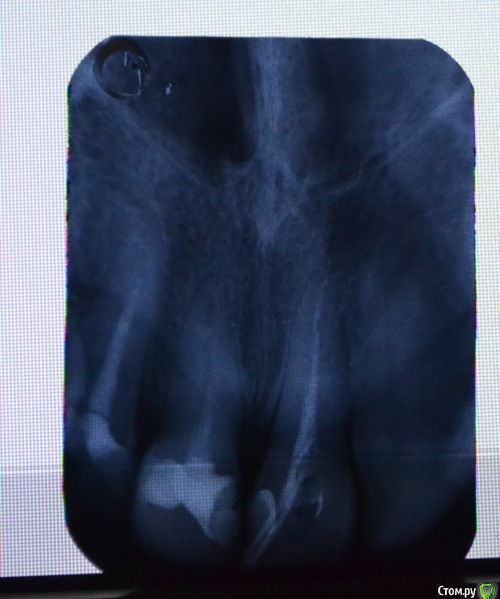

Llllll Опубликовано 28 июля, 2015 Автор Поделиться Опубликовано 28 июля, 2015 Перефотографировала, но не знаю какой снимок лучше, поэтому скинула все которые вышли) В среду канал сразу после этого рентгена запломбировали, к субботе начал очень сильно болеть, терпела, сегодня пошла на прием, открыли канал, но не скажу что стало лучше, может немножко. Боли пульсирующие, около носа, где верхушка зуба. Врач сказала что не знает что дальше делать( И почему оно болит( Ссылка на комментарий

Zlata-doctor Опубликовано 29 июля, 2015 Поделиться Опубликовано 29 июля, 2015 если вы не хотите потерять этот зуб ( а также и два соседних , которые тоже нуждаются в лечении), советую вам найти стоматолога, использующего современные протоколы эндодонтического лечения. Ни один из трех представленных на этих ужасных снимках зубов не пролечен как следует. Линкомицин, гидрокортизон, фонофорез итд -бегите оттуда. Извините за резкий тон, я Вам очень сочувствую. 1 Ссылка на комментарий

St. Опубликовано 11 августа, 2015 Поделиться Опубликовано 11 августа, 2015 По снимку все три зуба нуждаются в качественном лечении. Причем вполне возможно, что какие-то ощущения дает ещё соседний центральный зуб. Кусочка инструмента не увидела.Я понимаю, что найти хорошего стоматолога совсем не просто. Как минимум имейте ввиду, что оставлять зуб открытым - это плохо, колоть в десну антибиотики и гормоны, и выводить много-много чего-то там за пределы зуба - тоже не очень. 2 Ссылка на комментарий

Гарриевич Опубликовано 11 августа, 2015 Поделиться Опубликовано 11 августа, 2015 на этом снимке нет выраженных признаков периодонтита, но это не значит что его нет Ссылка на комментарий